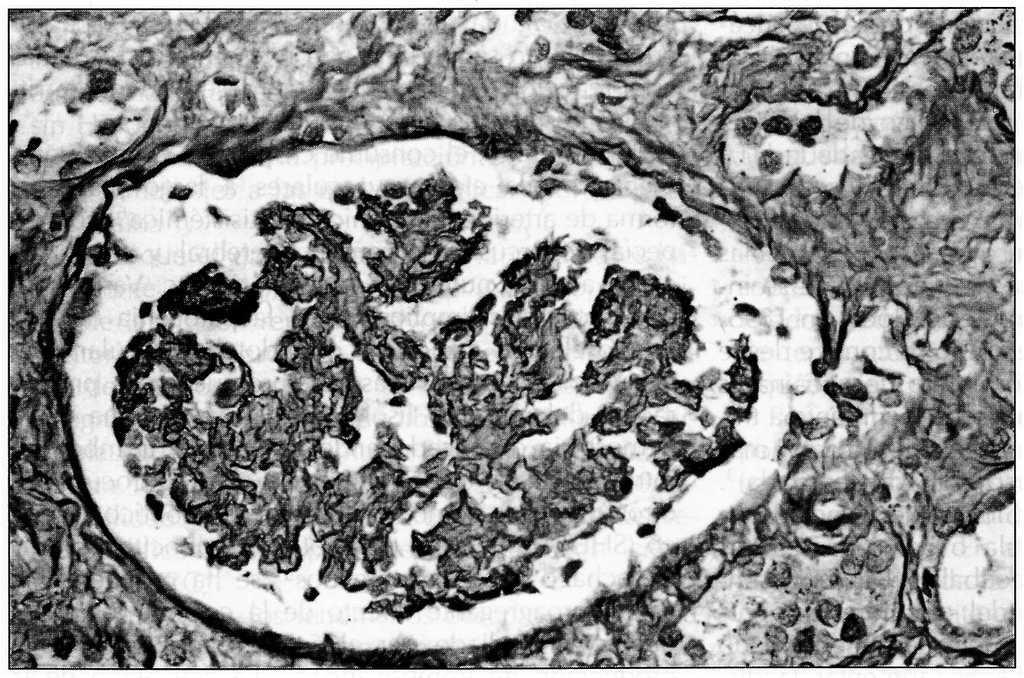

Acudió a emergencias de nuestro centro en agosto de 1999 por edemas maleolares de una semana de evolución, con cefalea occipital, somnolencia y pérdida de agudeza visual en los tres días previos a la consulta. En la exploración física inicial destacaron edemas maleolares y TA de 170/130 mmHg. Estando en emergencias presentó crisis comicial tonicoclónica generalizada seguida de disminución del nivel de consciencia y movimientos de descerebración, procediéndose a intubación orotraqueal (IOT) y a ventilación mecánica (VM). En la anamg/dla inicial destacó urea de 200 mg/di y creatinina de 4 mg/dl, con CK normales, siendo el resto de parámetros normales. El análisis toxicológico fue positivo para cocaína, benzodiacepinas, metoclopramida y posibles opiáceos. Una TAC cerebral demostró lesiones isquémicas, de baja perfusión sanguínea, occipitales y cerebelosas (figura 1).

Figura 1.